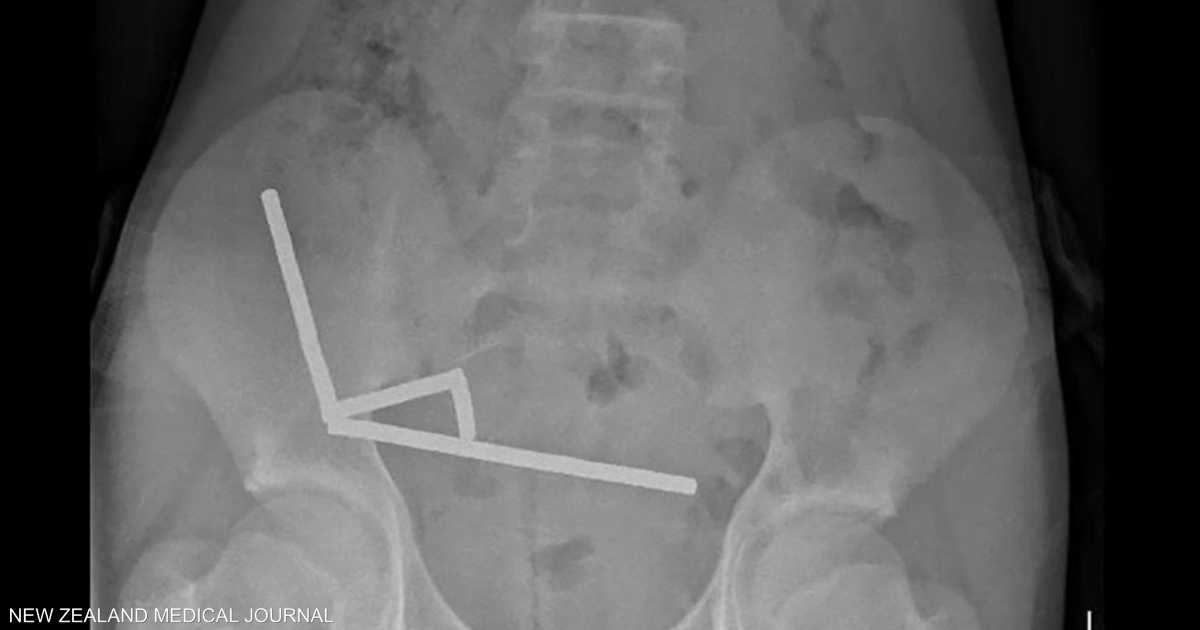

وأظهرت الأشعة أن المغناطيسات تكتلت معا في 4 خطوط مستقيمة داخل أمعاء المراهق، و”يبدو أنها كانت في أجزاء منفصلة من الأمعاء ملتصقة ببعضها البعض بسبب القوى المغناطيسية”، وفق الأطباء.